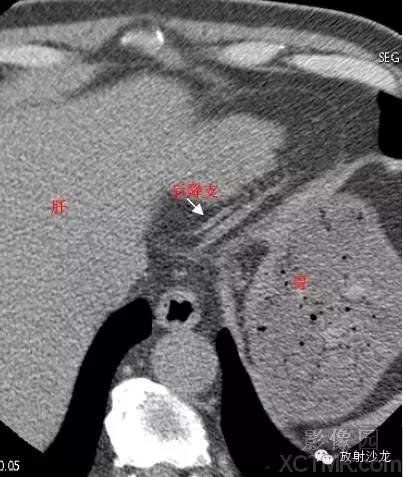

LCX -Left Circumflex Artery左回旋支

LAD -Left Anterior Descending Artery左前降支